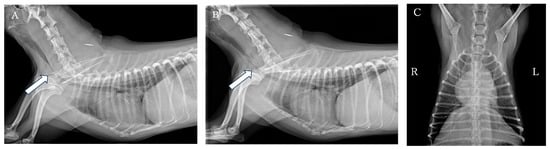

Tracheal stent fracture is a major complication of endoluminal tracheal stent (ELS) for canine tracheal collapse, and optimal management strategies remain unclear. A 4-year-old Yorkshire Terrier presented with respiratory distress caused by complete ELS fracture. Imaging and bronchoscopy revealed intraluminal protrusion of fractured stent segments, ventral tracheal cartilage invagination, and marked luminal deformation. A polypropylene linear prosthesis (PLLP) was selected as an external tracheal support. Its continuous band-like structure allowed broad and uniform reinforcement of the tracheal wall and redistribution of mechanical stress. PLLP placement successfully restored a near-normal tracheal contour and stabilized the fractured stent without introducing additional intraluminal material. Postoperative bronchoscopy confirmed improved tracheal patency, and no further deformation or stent damage was observed despite several months of altered airway dynamics associated with laryngeal paralysis. This case suggests that PLLP may represent a valid surgical option for managing tracheal stent fracture in dogs. Full article

Figure 1